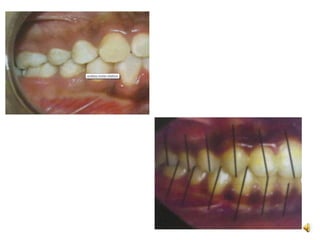

Crossbite

• It is a condition in which one or more teeth abnormally

malposed buccaly or lingually or labially with reference to

opposing teeth.

Open bite

• It is the failure of a tooth or teeth to meet their antagonist in

the opposite arch.

• It creats

– Difficulty in speech

– TMJ disorder

– Functional imbalance